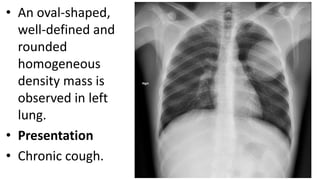

• An oval-

shaped, well-

defined and

rounded

homogeneous

density mass is

observed in

left lung.

Chronic

cough.

• Uncomplicat ed andintact, or unperforated , cysts may be diagnosed as round or oval-shaped lesions with regular fine margins.

• An oval- shaped,well- defined and rounded homogeneous density mass is observed in left lung. Chronic cough.